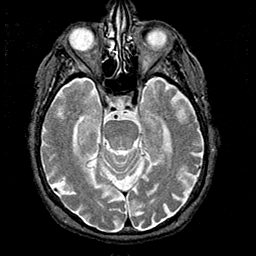

Alzheimer's disease MR T2-weighted -- Slice #17

[Home][Help][Clinical][Tour 1][Tour 2] Slice 17